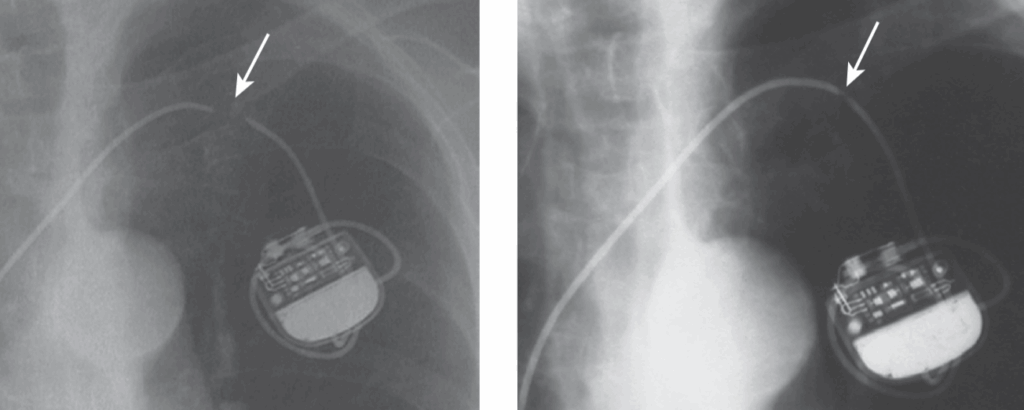

A 72-year-old patient was admitted for stroke. He had been implanted with a dual-chamber pacemaker 2 months ago for sinus dysfunction. Interrogation of the pacemaker was normal and did not disclose any atrial arrhythmias that may have explained the neurological event. A chest X-ray was performed and is shown

The ventricular lead is in the LV via a patent foramen ovale

• The PA view the ventricular lead would be expected in a lower position

• The lateral view shows the V lead to be posterior, whereas an RV lead would be anteriorly located.

• LV capture results in a negative QRS in lead I (which may be observed occasionally also with RV pacing) and an RBBB QRS morphology.